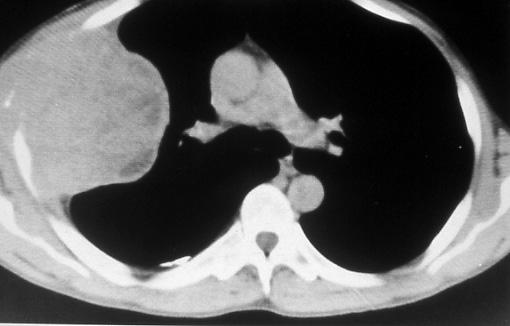

Fig. 13b: Computed tomographic scan of the chest shows to better advantage the peripheral tumor in the right lung with rib destruction and extension through chest wall, T3.